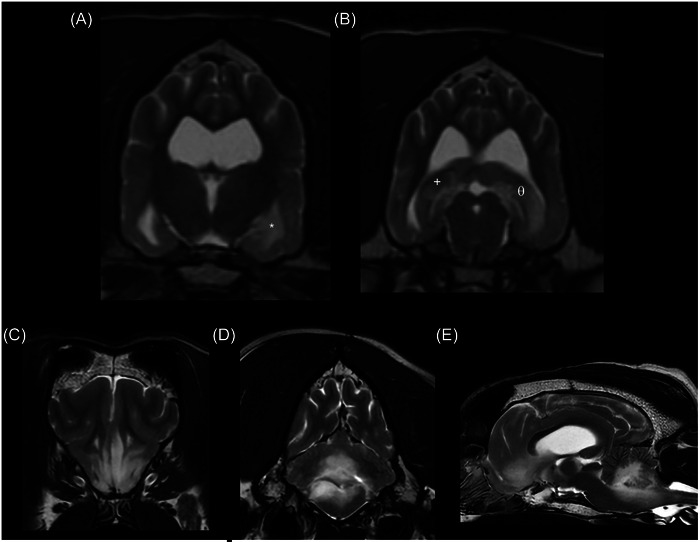

A 10-year-old female spayed boxer was treated with stereotactic radiotherapy (SRT) for a suspected glioma in the left piriform lobe. The intra-axial lesion was T2 hyperintense, T2 FLAIR hyperintense, T1 hypointense, and did not uptake contrast. Imaging was performed with an MRI every 3 months, and at the 6-month recheck, new lesions in the left hippocampus and right piriform lobe were evident without clinically apparent neurological progression. A second course of SRT was prescribed for the new lesions. Euthanasia was elected 14 months after the first course of SRT, and necropsy confirmed oligodendroglioma with drop metastasis.

Abstract Image